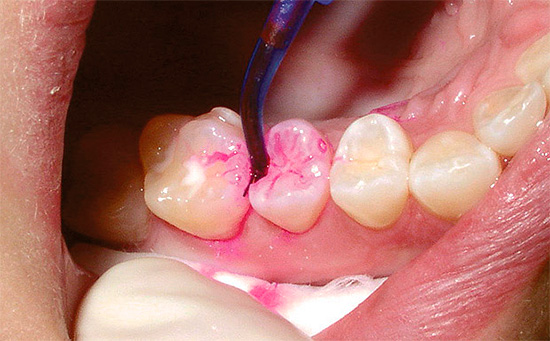

Degli ingredienti attivi nei marcatori di carie, la fucsina acida è il più comunemente usato - un noto colorante sintetico che ha un colore rosso intenso in soluzioni acquose. La foto mostra come le parti cariate del dente sono macchiate con esso:

Meno comunemente, il blu di metilene viene utilizzato per rilevare la carie, che funziona in modo simile alla fucsina, ma colora di blu le aree interessate.